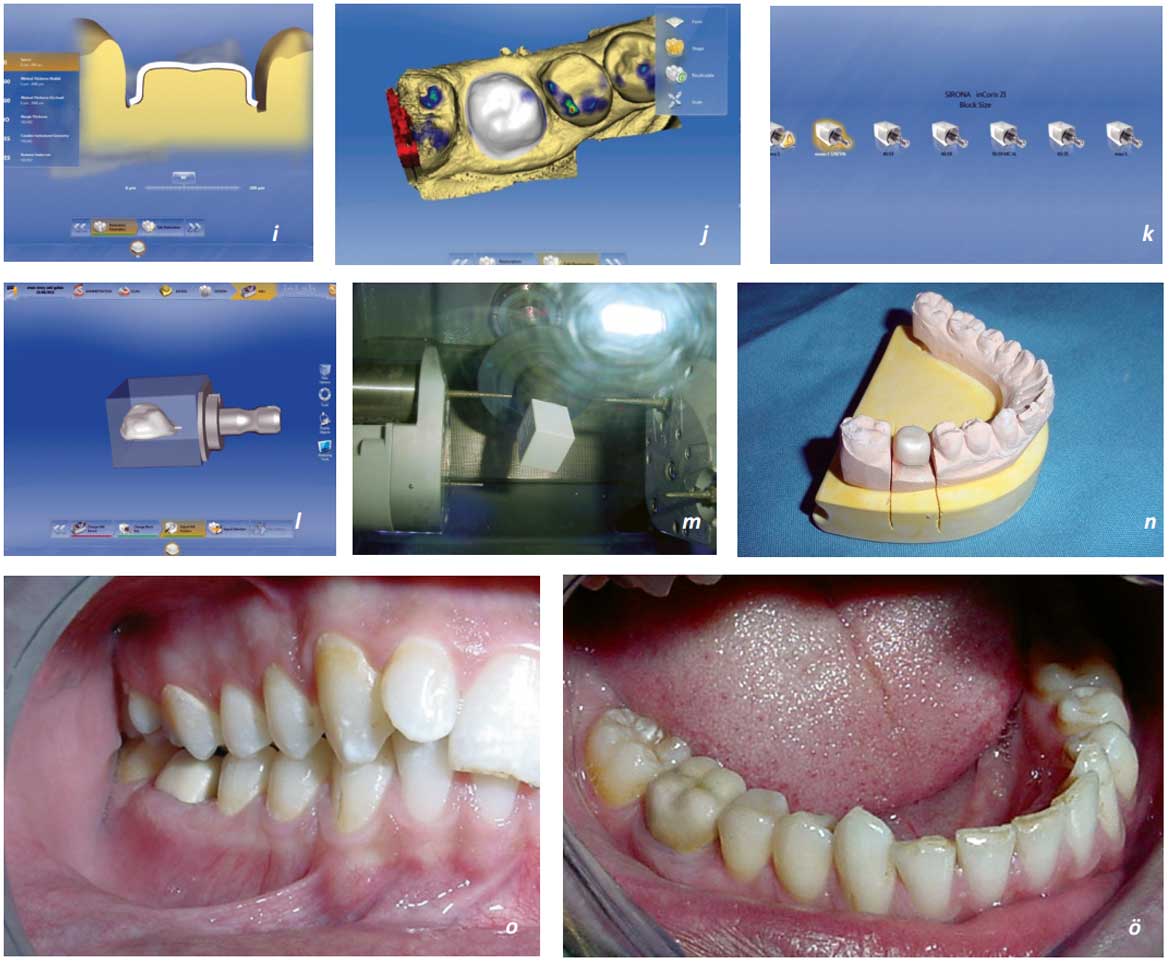

Bolum 9 4 Tam Seramik Restorasyon Ozellikler

Sabit Protezler Bolum 9 2 Cad Cam Ve Freze Teknolojisi

Cerec Dis Hekimliginde Cad Cam Uygulamasi